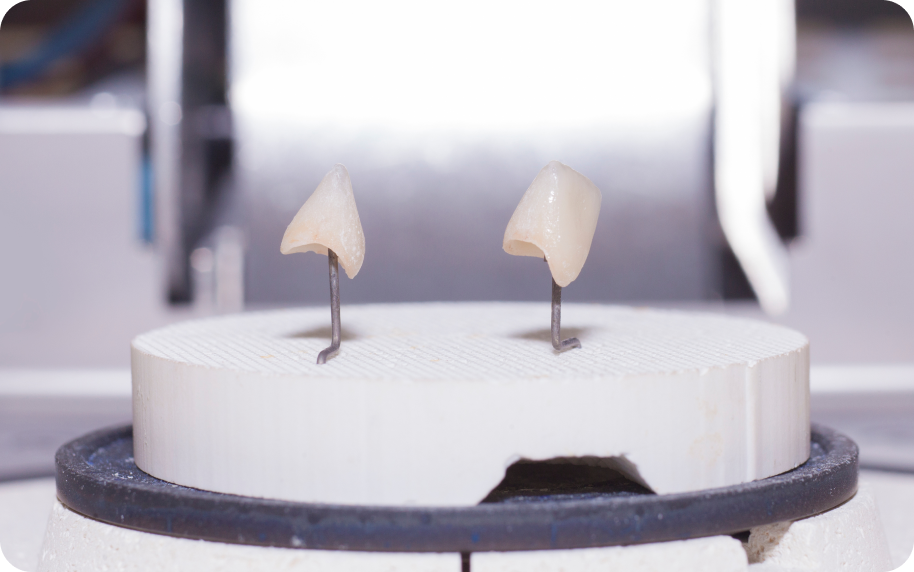

- Les facettes

Les facettes conviennent surtout lorsque la dent reste peu délabrée et que l’objectif principal concerne l’esthétique. Elles corrigent la forme, la teinte ou certains défauts visibles. Dans un projet global, elles trouvent souvent leur place au niveau des dents antérieures.

Puis, il sélectionne les solutions prothétiques selon le cas. Dans certaines situations, des restaurations provisoires ou des maquettes d’essai peuvent aider à valider le projet avant la phase définitive. Ces outils permettent d’ajuster certains détails et de sécuriser le résultat final.